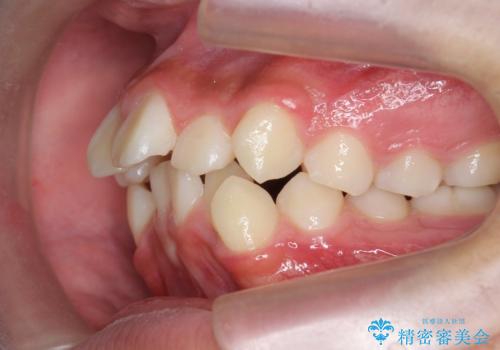

- 前歯のがたつきが原因で歯ブラシしづらい、見た目を改善したい!と矯正治療を希望され来院されました。

スペースの不足が見られるため、小臼歯の4本抜歯を行いマルチブラケットを用いた矯正治療を計画します。

噛み締めが強く、治療に時間がかかりましたが矯正治療の仕上がりに満足いただくことができました。